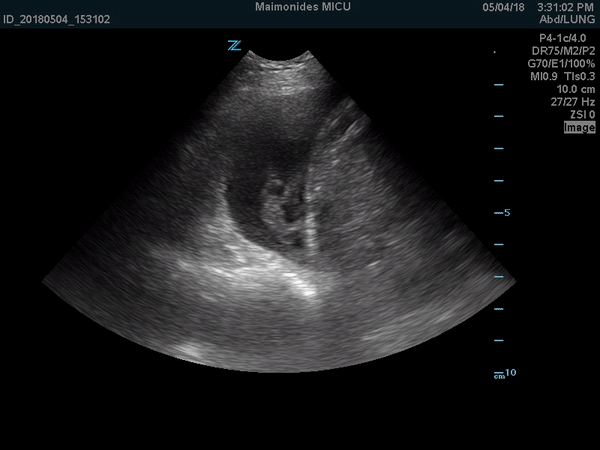

further management. In the ER, he was febrile up to 102oF and had leukocytosis of 15.6 X 109/L with neutrophilia of 90.3%. A bedside ultrasound was performed which is shown in video 1.

Video 1: Ultrasound video on a phased array probe shows the swirling movement of the cellular debris, fibrin strands and septations in the pleural cavity.

Complicated pleural effusions appear as exudative effusions on lung

ultrasounds and have a non-homogenous echogenic pattern due to cellular

debris, fibrin strands and septations. Cardiac and respiratory movements

lead to swirling movements of these cellular debris, fibrin strands and

septations, giving us a dynamic presentation of pleural effusion on

ultrasound imaging. The presence of cellular debris and septations in

parapneumonic effusions may indicate the presence of empyema or a

complicated parapneumonic effusion which requires drainage and a longer

duration of antibiotics.(1)

In order to identify a pleural effusion, intensivists must first

locate important anatomical landmarks which include the chest wall,

diaphragm and sub-diaphragmatic structures, such as the spleen or the

liver and the lung (Figure 1). Once identified, the effusion can be

further described by its echogenicity and quantification.

Figure 1: Anechoic space above the diaphragm with visible linear echogenic septations.